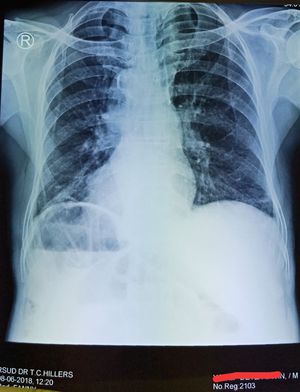

DEXTROCARDIA with SITUS INVERSUS

the patient came to the hospital with the migrating pain at hemithorax dextra

Situs inversus totalis....

Kartagener syndrome

Situs inversus